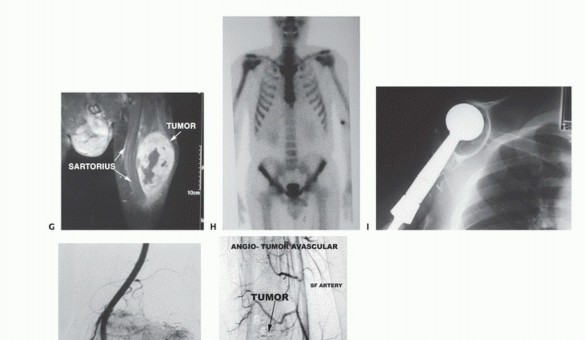

- Computed Tomography (CT): The modality of choice for assessing fine osseous detail, cortical integrity, and matrix mineralization. Thin-slice (≤1 mm) helical CT allows for precise 3D reconstructions. Intravenous contrast is essential to delineate the relationship of the soft tissue mass to major vascular bundles. Chest CT is mandatory for staging to rule out pulmonary metastases.

- Magnetic Resonance Imaging (MRI): The gold standard for evaluating the local extent of the tumor. It accurately defines the intramedullary extent (allowing calculation of bone resection levels), soft tissue extension, joint involvement, and the presence of skip metastases. T1-weighted images best define marrow replacement; T2-weighted and STIR sequences highlight peritumoral edema and the soft tissue mass. Contrast enhancement differentiates cystic from solid components and clarifies neurovascular proximity.

- Bone Scintigraphy (Technetium-99m): Utilized to detect polyostotic disease and skeletal metastases. The three-phase bone scan assesses biologic activity; a "tumor blush" in the flow/pool phases indicates high vascularity typical of malignancy.

- Angiography and Venography: While largely supplanted by CT/MR Angiography, traditional angiography can map complex vascular displacements, identify feeding vessels for preoperative embolization (critical for hypervascular metastases like renal cell carcinoma), and assess the patency of collateral circulation prior to major vessel ligation. Venography can identify tumor thrombus or extrinsic venous compression.

- PET-CT (FDG): A functional imaging modality measuring glucose metabolism. It is increasingly the standard of care for total body staging, identifying occult metastases, and monitoring the metabolic response to neoadjuvant chemotherapy (measured by the Standardized Uptake Value, SUV).

Biopsy is the final, definitive step in staging. It must be meticulously planned by the treating orthopedic oncologist. Poorly executed biopsies can contaminate tissue planes, necessitating amputation instead of limb salvage. Core needle biopsy is preferred; if open incisional biopsy is required, it must be longitudinal, meticulously hemostatic, and placed entirely within the planned definitive resection tract.